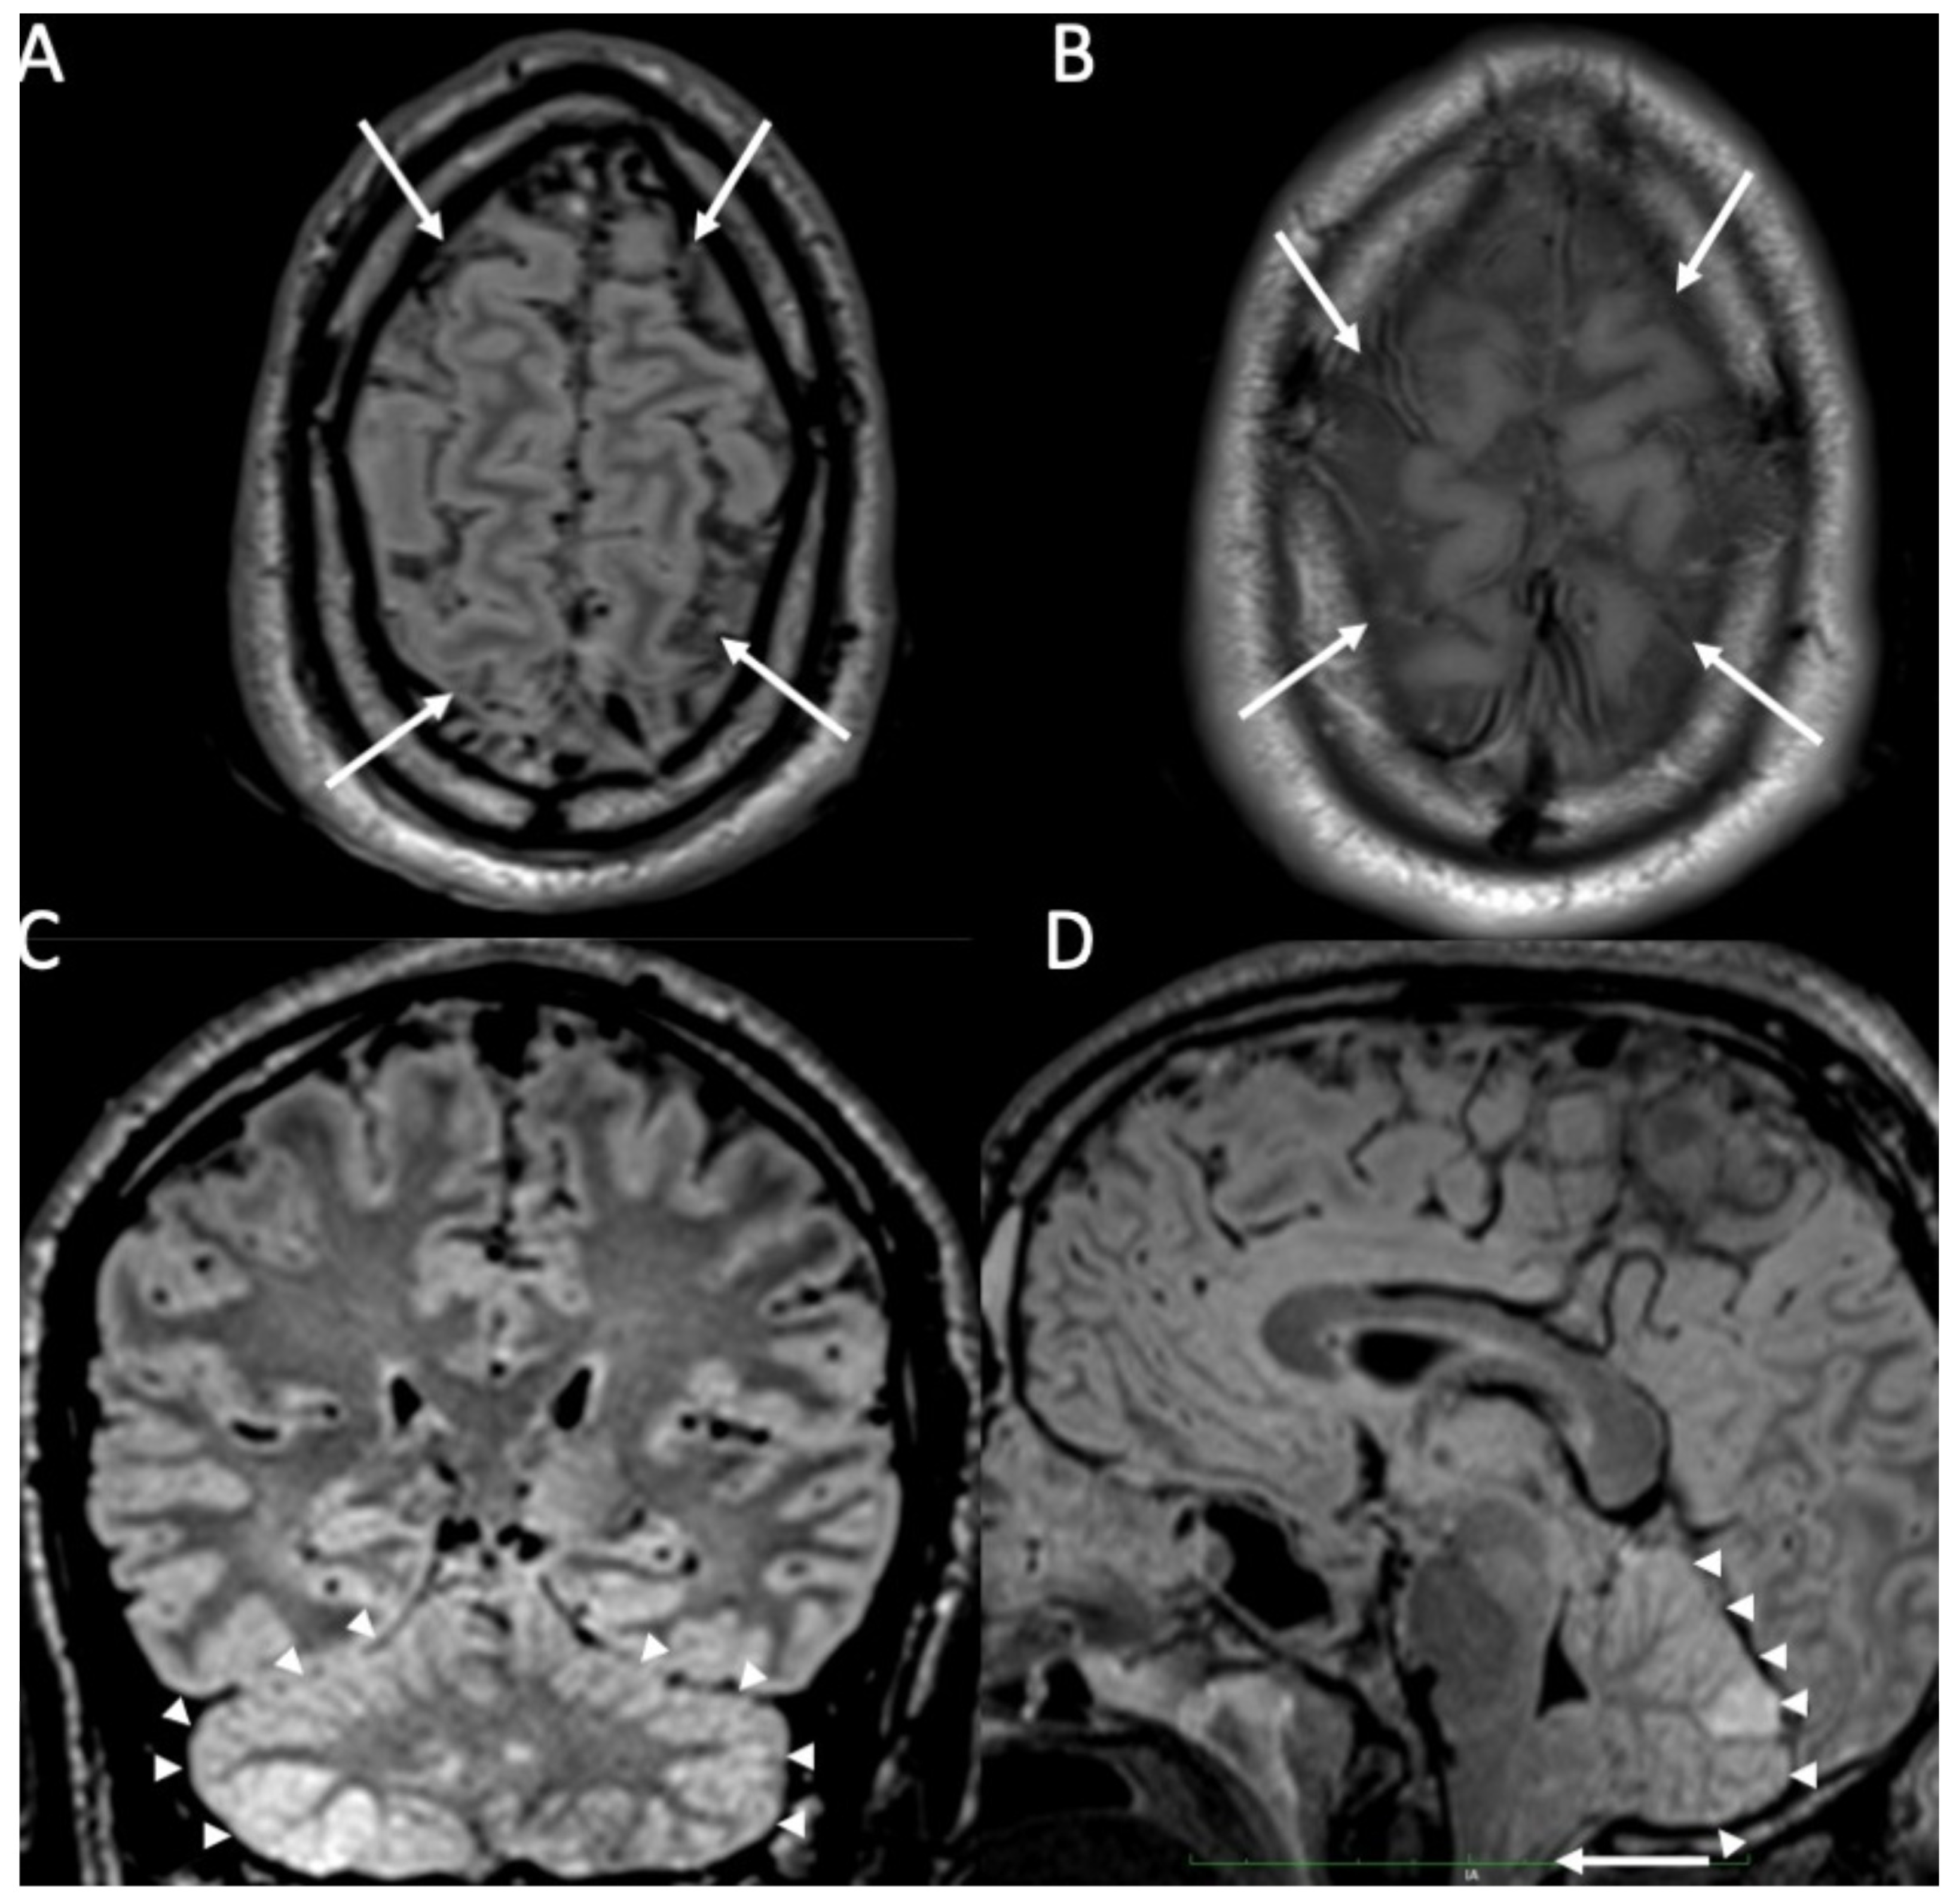

| Piogenic Meningitis | • Cerebrospinal fluid hyperintensity in T1 and FLAIR • Restricted diffusion of the subarachnoid spaces • Meningeal enhancement on T1 and FLAIR |

2. Piogenic Meningitis

3. Tuberculous Meningitis/Meningoencephalitis